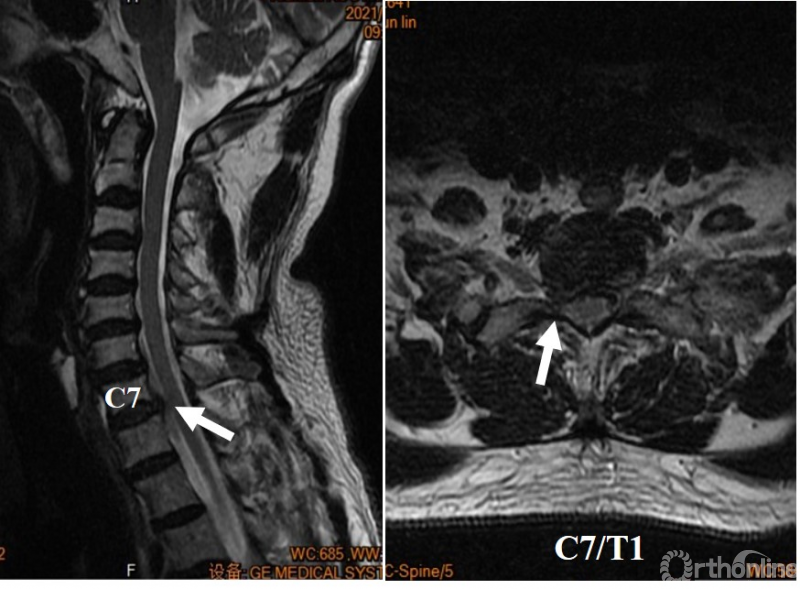

心电图提示窦性心律,ST-T轻度压低。胸部X线、胸部CT、心脏彩超及心肌酶均未见明显异常。颈椎X线提示颈椎退变及前纵韧带骨化(图A),颈椎MRI提示C7-T1椎间盘突出导致右侧C8神经根严重压迫(图B)。经科室讨论明确诊断为神经根型颈椎病及颈源性胸痛后,进行C7/T1的ACDF手术(图C),术后患者胸痛症状明显好转(VAS=2分),右手麻木症状消失,肌力也逐渐恢复。

图B 术前颈椎MRI提示右侧C8神经根受压